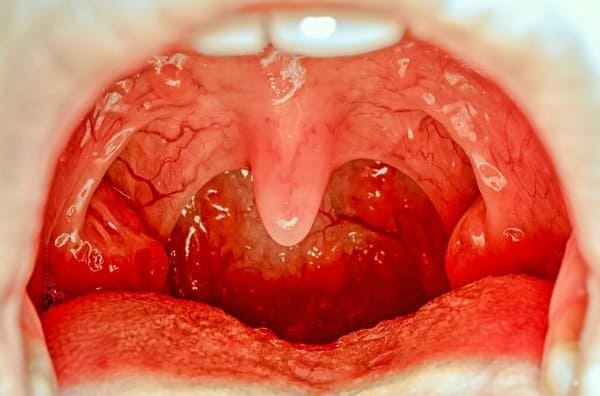

El paladar es la parte superior de la cavidad bucal y su función es la de separar la nariz de la boca. Gracias a esto, se puede llevar a cabo el proceso de alimentación sin que se produzcan problemas en la función respiratoria.

Se divide en dos partes: el paladar duro, que es justo la zona que se encuentra detrás de los dientes, y el paladar blando, situado en la parte posterior de la cavidad bucal. La mayor parte de las quemaduras se producen en el paladar duro ya que es donde rozan los alimentos y sustancias que las provocan.

A las lesiones causadas por quemaduras en el paladar también se las conoce con el nombre de aftas, una especie de ampollas rellenas de líquido que, una vez que desaparecen, no dejan cicatrices ni ningún otro tipo de señal.

Tiene una gran cantidad de terminaciones nerviosas por lo que cuando se produce una quemadura, causa dolor y molestia. Aunque hay diversos grados de quemadura, por lo general las que se producen en el paladar suelen ser de primer grado. Existen distintas causas por las que el paladar puede sufrir quemaduras.